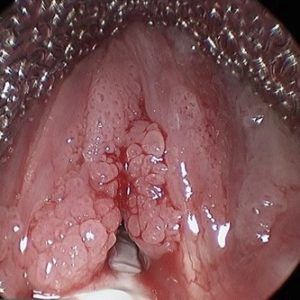

При огляді слизової горла помітні незначні вирости, соскоподібного форми, іноді нагадують гребінь або горбок. Шорстка, зморшкувата поверхню. Колір зливається із загальним тоном слизової, іноді світліше, ближче до білого.

Папілома в горлі присутній в одиничному екземплярі або має множинні осередки. Захворювання переходить в хронічну. Локалізується на голосових зв'язках, шлуночках гортані, в подскладочном просторі, язичку (рідко) і надгортаннике.

Фото операції з видалення папилломатоза в горлі